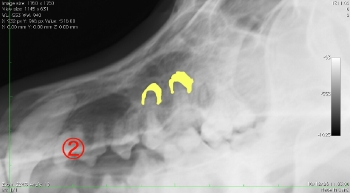

● 歯の破折 3 : 根先膿瘍の放置による目の下の開放創

この3枚の写真に示されるように①は根先部に膿瘍が認められます。②は膿瘍部分に黄色く色づけをしてみました。③は逆サイドの正常な写真になります。![]()